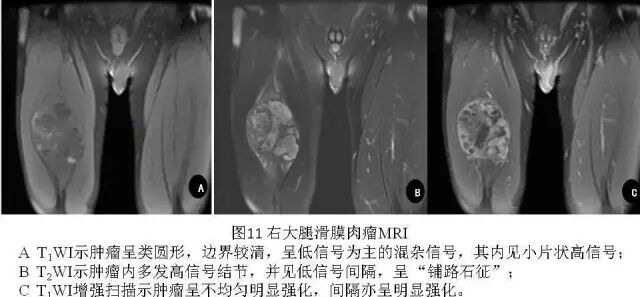

3.MRI

肿瘤在MRI上平扫表现为类圆形或分叶状肿块,T1WI信号多与肌肉相似,肿瘤合并出血时可出现小斑片状高信号区。少数因瘤内广泛的出血,整个肿瘤可呈高信号。T2WI上信号多不均匀,肿瘤内常出现高、等、低三种信号混合存在的征象,有学者称之“三信号征”(也有学者称之“三重信号征”或“三联征”)(图9、图10),是滑膜肉瘤MRI较为特征性征象之一。T2WI抑脂序列上滑膜肉瘤可呈多个大小近似的卵石状结节,其间存在低信号间隔,似铺路石状,称之为“铺路石征”(也有学者称之“卵石征”)(图11),也是滑膜肉瘤MRI较为特征性征象之一。部分病例(15%~25%)可出现液-液平面,为非特异性表现。常规MR增强扫描,肿瘤呈片絮状明显不均匀强化,分隔可呈明显强化(图11)。